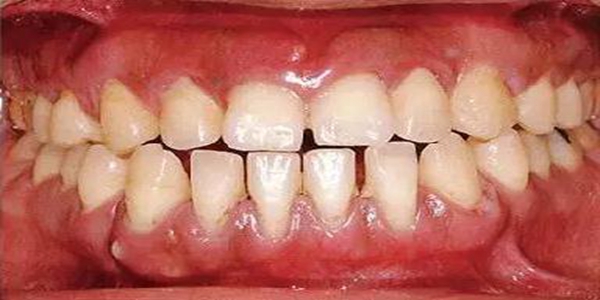

●33歲男性 侵襲性牙周炎廣泛型口腔內(nèi)照片

33歲男性,吸煙(1天10根,12年吸煙史)。菌斑控制狀況不好,牙周探診全頜牙周袋深5~10mm之外,全頜性牙周袋出血,部分牙周袋有排膿現(xiàn)象。X片可觀察到全頜性重度骨吸收。通過以上檢查可診斷出該患者為侵襲性牙周炎廣泛型。視診可知牙齦雖然有炎癥,但沒有出現(xiàn)嚴重浮腫,沒有大量牙結石沉積。